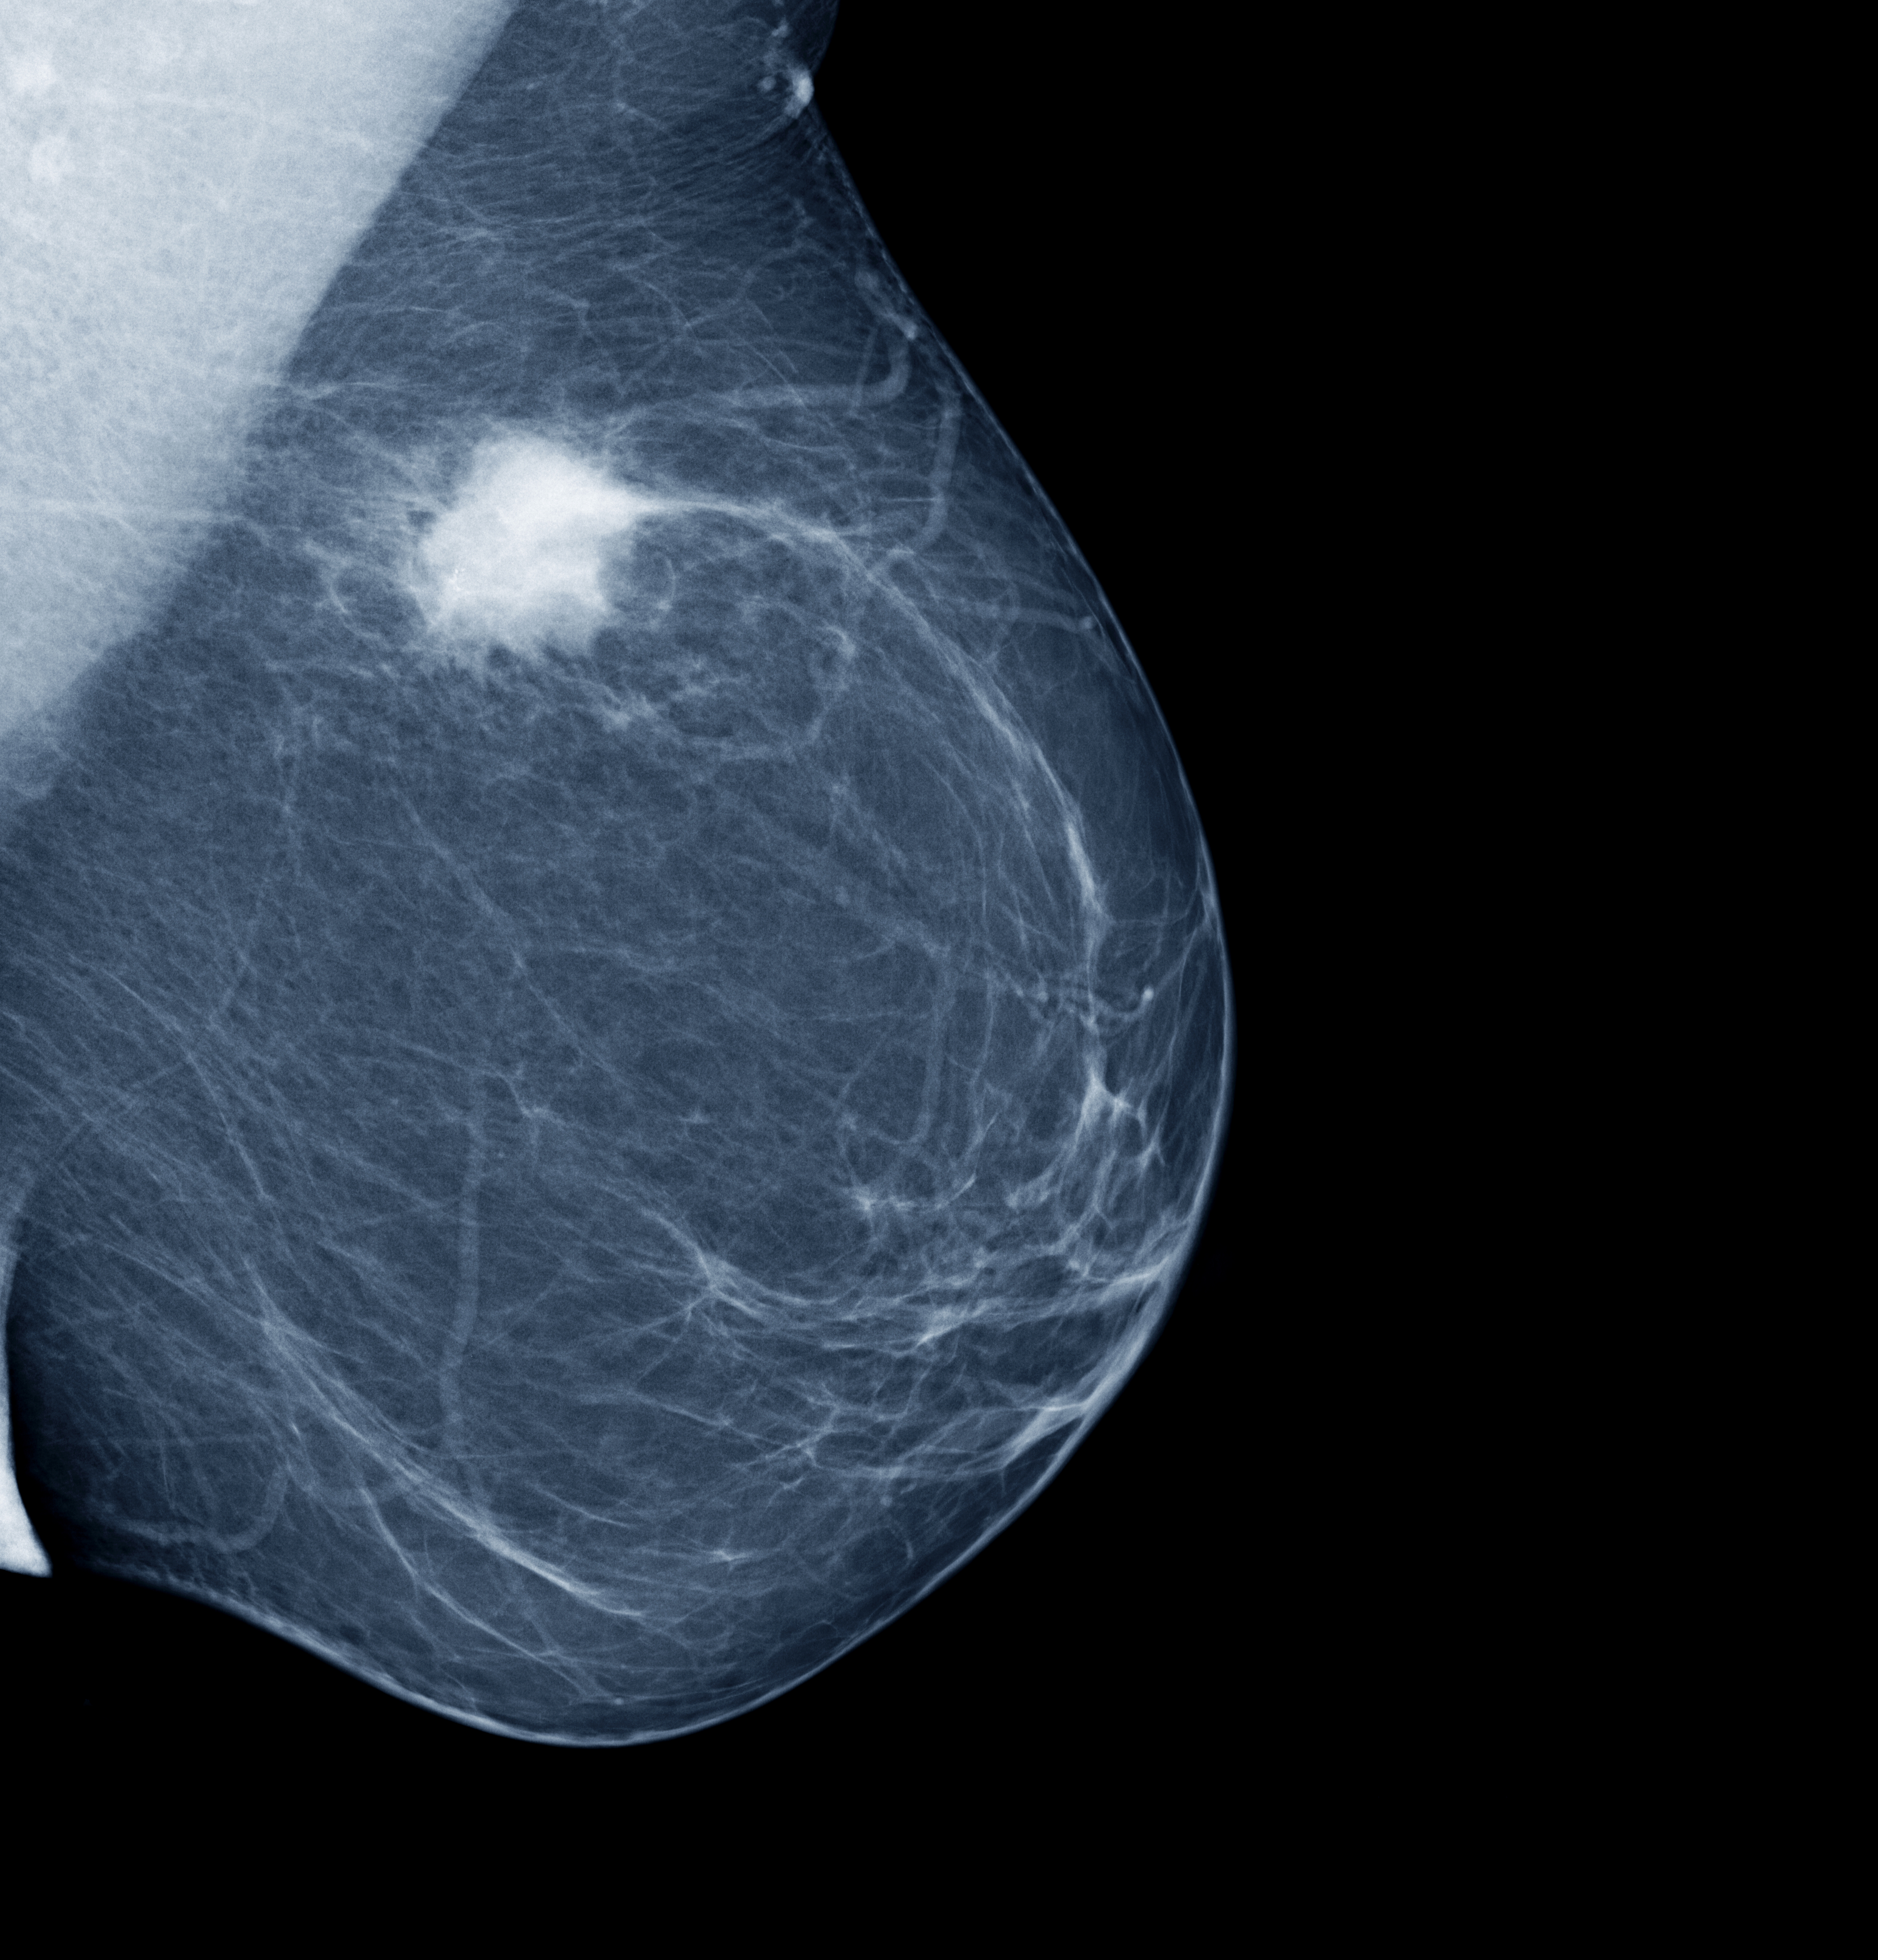

Фиброаденома молочной железы - доброкачественное образование, которое часто встречается у женщин. Оно может быть обнаружено при помощи различных методов диагностики, включая маммографию. Ниже представлены фотографии, помогающие понять, как выглядит данное заболевание.

Опухоль на снимке маммографии

Маммография и ее роль в диагностике фиброаденомы молочной железы

Маммография - это рентгенологическое исследование молочных желез. Оно позволяет выявить различные изменения в тканях, включая фиброаденому. На маммограммах можно увидеть структурные особенности опухоли и отследить ее динамику во времени.